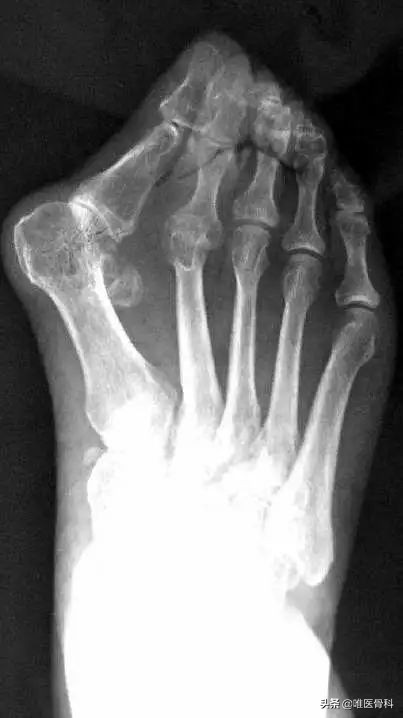

我们一般依据指外翻的程度还有患者的症状,将外翻大致分为4个阶段,如果您发现您的指已经越来越向外了,那就应该尝试对号入座,引起足够重视了。

大指外翻10°左右,一般没有疼痛感,脚掌有轻微的茧,一般不影响行走,但穿高跟鞋时会有些痛。

大指外翻10~20°左右,第一和第二脚趾有明显的向外侧挤压,脚掌明显变宽,足底脚茧明显。关节和韧带发生炎症,长时间行走的话,会出现大趾根部疼痛和脚掌疼痛。

大趾外翻20~40°左右,足趾重叠。正常人足底有两个向上的拱起,称为横弓和纵弓,这样走起路来比较有弹性,比较省力,而这个阶段的外翻患者,横弓因为足趾的挤压,基本已经消失、塌陷——形成我们所谓的“扁平足”。

有的患者足底经常摩擦,产生鸡眼,老茧,脚垫。脚后跟出现疼痛,行走时难以把握平衡。

大指外翻40°以上,指严重重叠,足趾在走路时基本上派不上什么用场,扁平足,十分疼痛,行走困难。